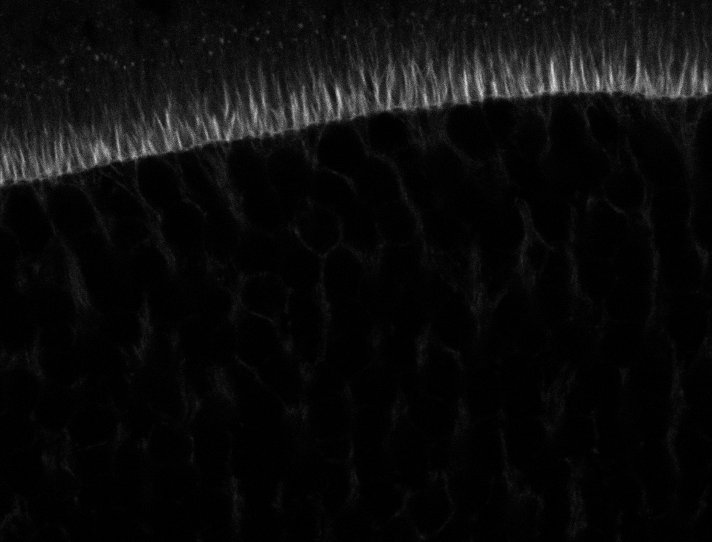

Actin